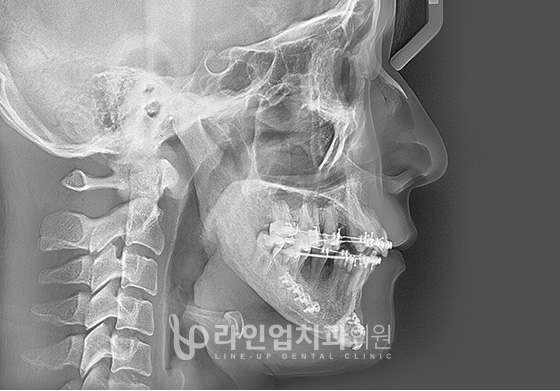

하악수술 방법

01

어금니 뒷쪽의 턱뼈에서 턱관절사이를 절골합니다.

02

수술계획에 의한 위치로 이동시킵니다.

03

플레이트로 턱을 고정합니다.

전후사진

치료전 Before